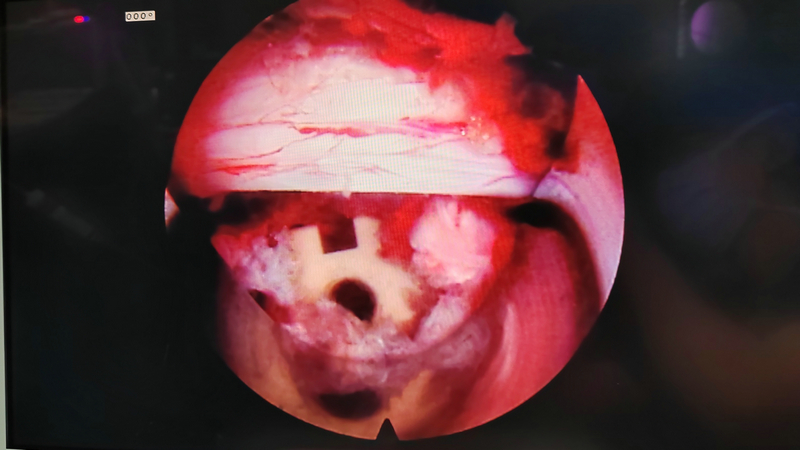

患者王某某,女,49歲,該患者5年無明顯誘因出現(xiàn)腰部疼痛伴左下肢放射痛、麻木不適,予以針灸、理療等對癥治療,病情時(shí)輕時(shí)重。3月前勞累后再次出現(xiàn)上述癥狀,且癥狀進(jìn)行性加重,嚴(yán)重影響生活,聽村民介紹后到市二院骨傷科三病區(qū)就診。經(jīng)檢查后,腰椎動(dòng)力位片提示腰椎不穩(wěn);腰椎核磁提示腰4/5椎間盤巨大突出,腰4/5椎管狹窄。副院長姚雄兵帶領(lǐng)骨三科團(tuán)隊(duì)立即組織病例討論,仔細(xì)詢問病史及體格檢查,結(jié)合影像學(xué)檢查,全面評估后與患者及家屬溝通,確定行“經(jīng)皮脊柱內(nèi)鏡輔助下腰椎椎體間植骨融合內(nèi)固定(ENDO-PLIF)術(shù)”。手術(shù)邀請甘肅中醫(yī)藥大學(xué)附屬醫(yī)院椎間盤中心主任李元貞指導(dǎo),在手術(shù)麻醉科的配合下術(shù)程順利,術(shù)后患者左下肢放射痛、麻木癥狀完全緩解,手術(shù)效果良好。

與傳統(tǒng)的腰椎后路開放減壓手術(shù)及通道下的MIS-TLIF手術(shù)相比,經(jīng)皮脊柱內(nèi)鏡后路腰椎ENDO-PLIF手術(shù),創(chuàng)傷更小,神經(jīng)根及硬膜囊顯露清晰,且最大限度的保護(hù)了脊柱骨骼、韌帶及肌肉的完整性,對脊柱穩(wěn)定性影響較小,術(shù)后患者感受更佳,康復(fù)更快,脊柱的ENDO-PLIF微創(chuàng)手術(shù)必將成為未來的發(fā)展趨勢。